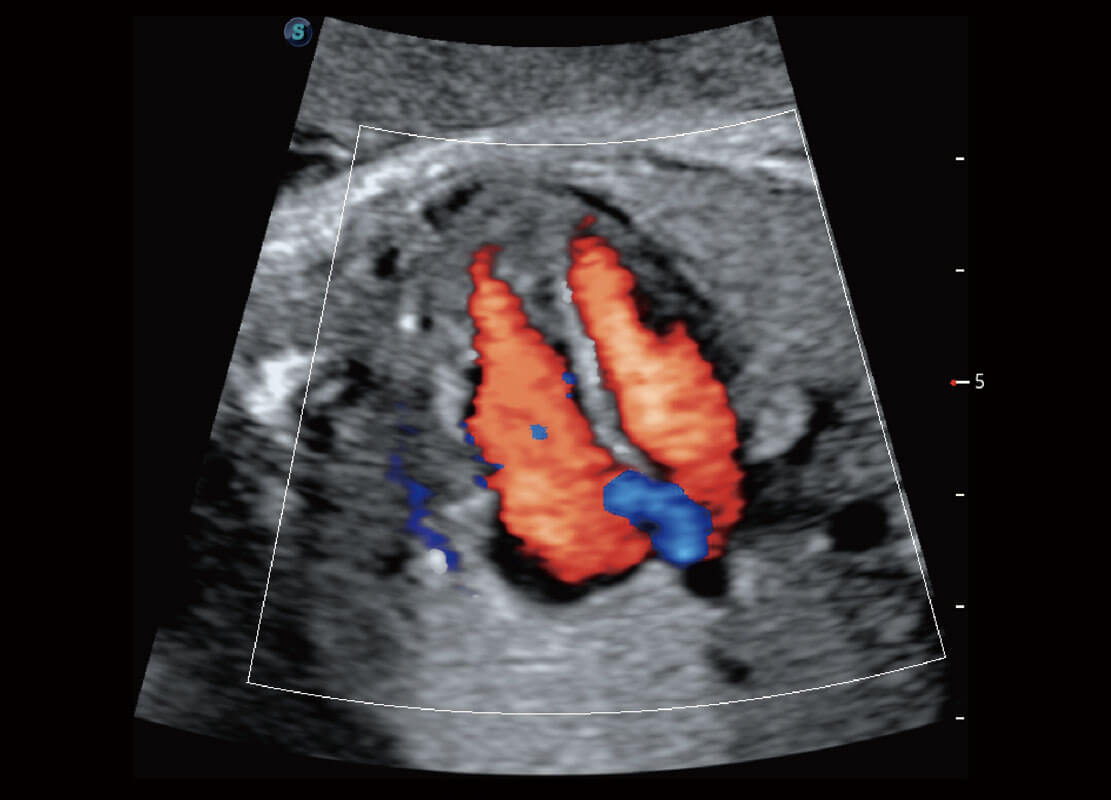

P60優(yōu)異的圖像質(zhì)量搭載??铺筋^,在婦科基礎(chǔ)疾病的診斷、卵泡生長的監(jiān)測、輸卵管通暢情況的判別等方面為您提供生殖應(yīng)用方案。

腔內(nèi)婦科-卵巢